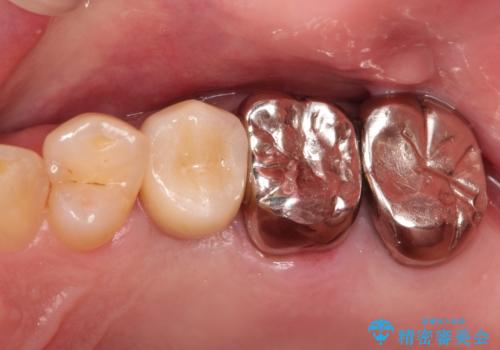

インプラントによる治療は隣在歯を削らずに咬合回復できるという利点があります。

セラミッククラウンにより自然な見た目で修復できました。